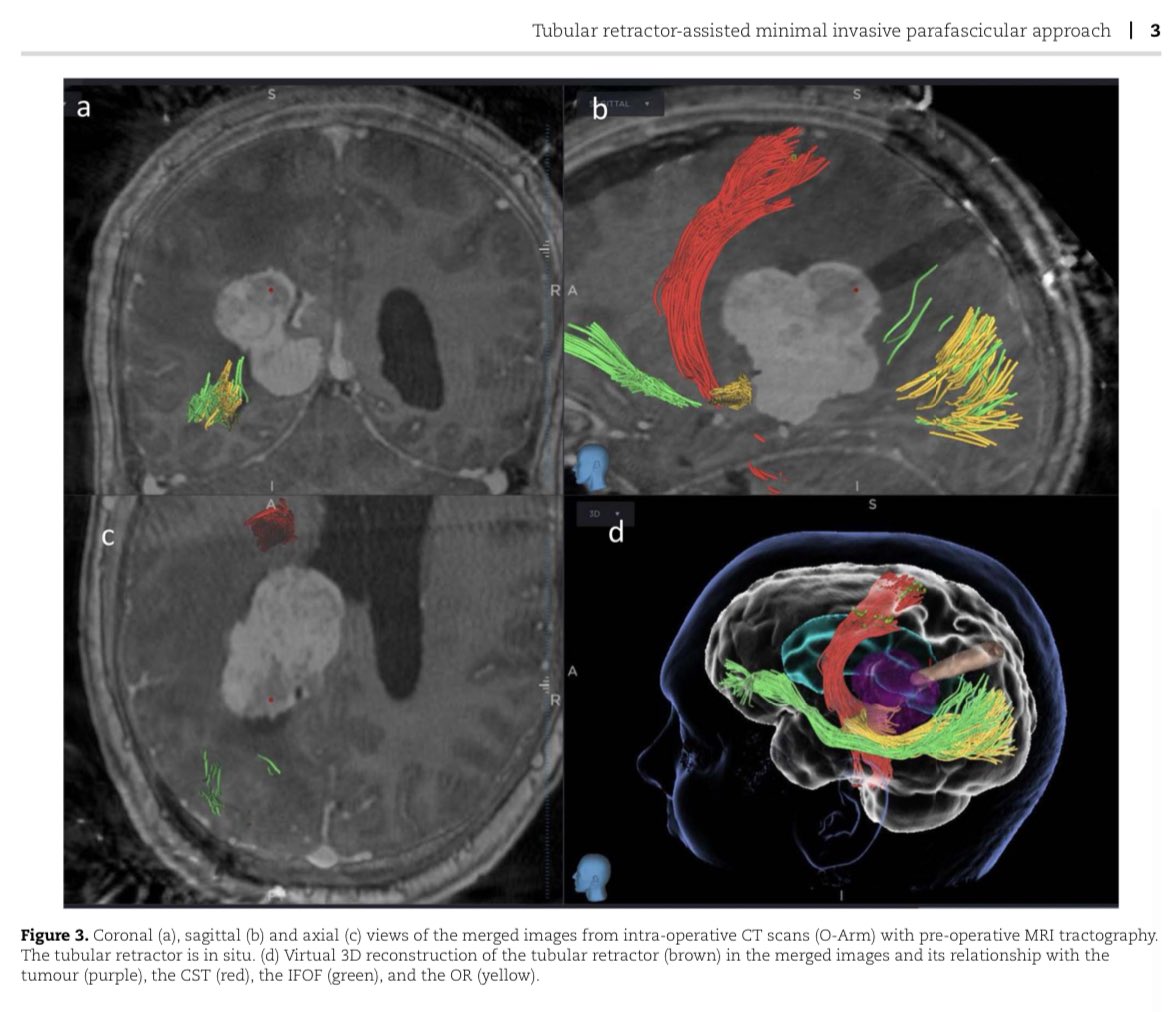

Latest Publication Alert!‼️ A Technical Note on use of O-Arm navigation in tubular retractor-associated MIPS approach in @JSCR_OUP. Read more: https://t.co/LXLRsh6OAM 👌@aelhagSN @NeurOktay @lavrador_jose @saspist

@NeurOktay

Very happy to share our latest publication, describing the intra-operative use of the O-Arm to aid tubular retractor localisation during minimally-invasive parafascicular surgery (MIPS). Thank you @lavrador_jose @saspist @KingsNeuro https://t.co/UaO41rIXCv

Tweet card summary image

Abstract. Trans-sulcal minimally invasive parafascicular surgery is an emerging technique to approach deep lesions with minimal brain retraction. Localizat